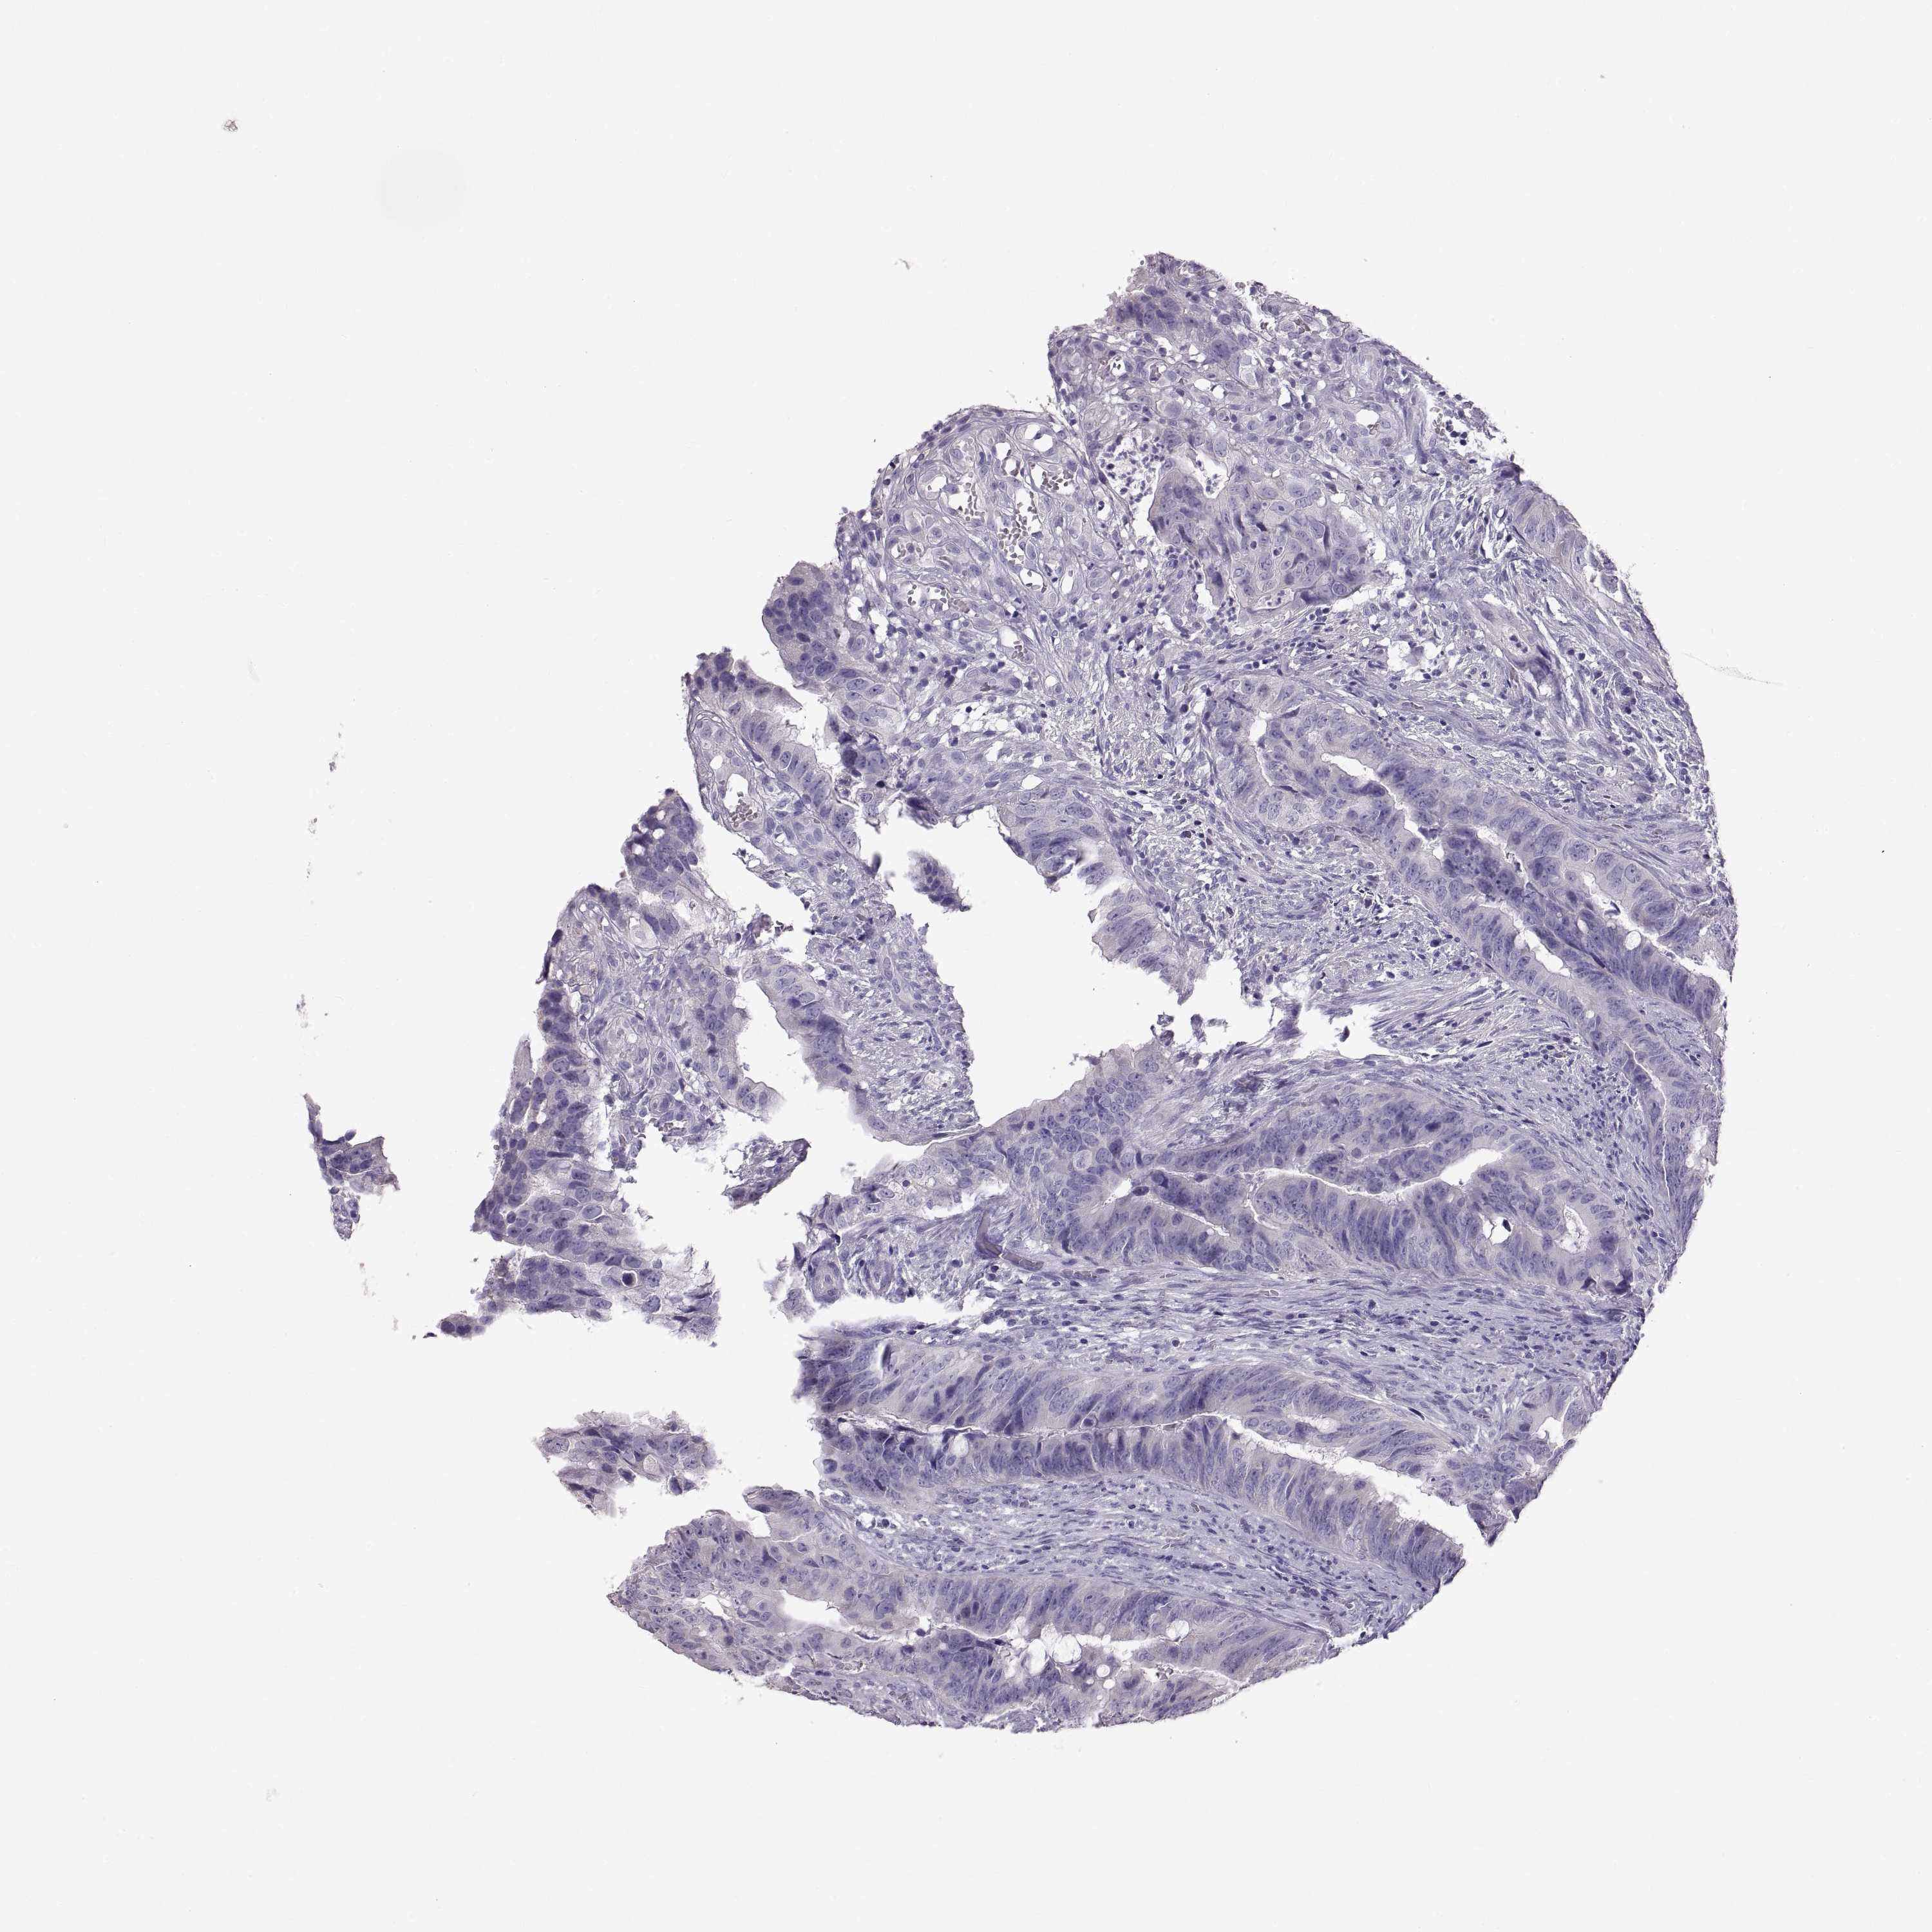

CANCER COLORECTAL CANCER Show tissue menu

Colorectal cancer

Rectum adenocarcinoma